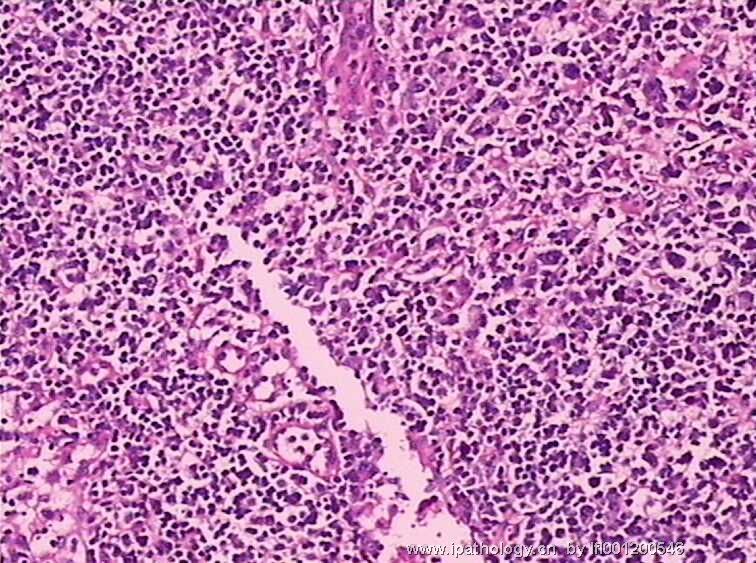

女,45岁,发现颈部多个淋巴结肿大,体查时发现全血细胞减少.取最大的淋巴结送检.

图3

淋巴结结构破坏,有明显异常细胞,结合病史,考虑恶性,淋巴瘤、白血病?不知血片分类怎样?待组化和专家讲解。谢谢!

恶性,考虑淋巴造血系统肿瘤。NHL或白血病。

恶性是肯定,就是要排除转移的恶黑。再考虑原发的非何杰金